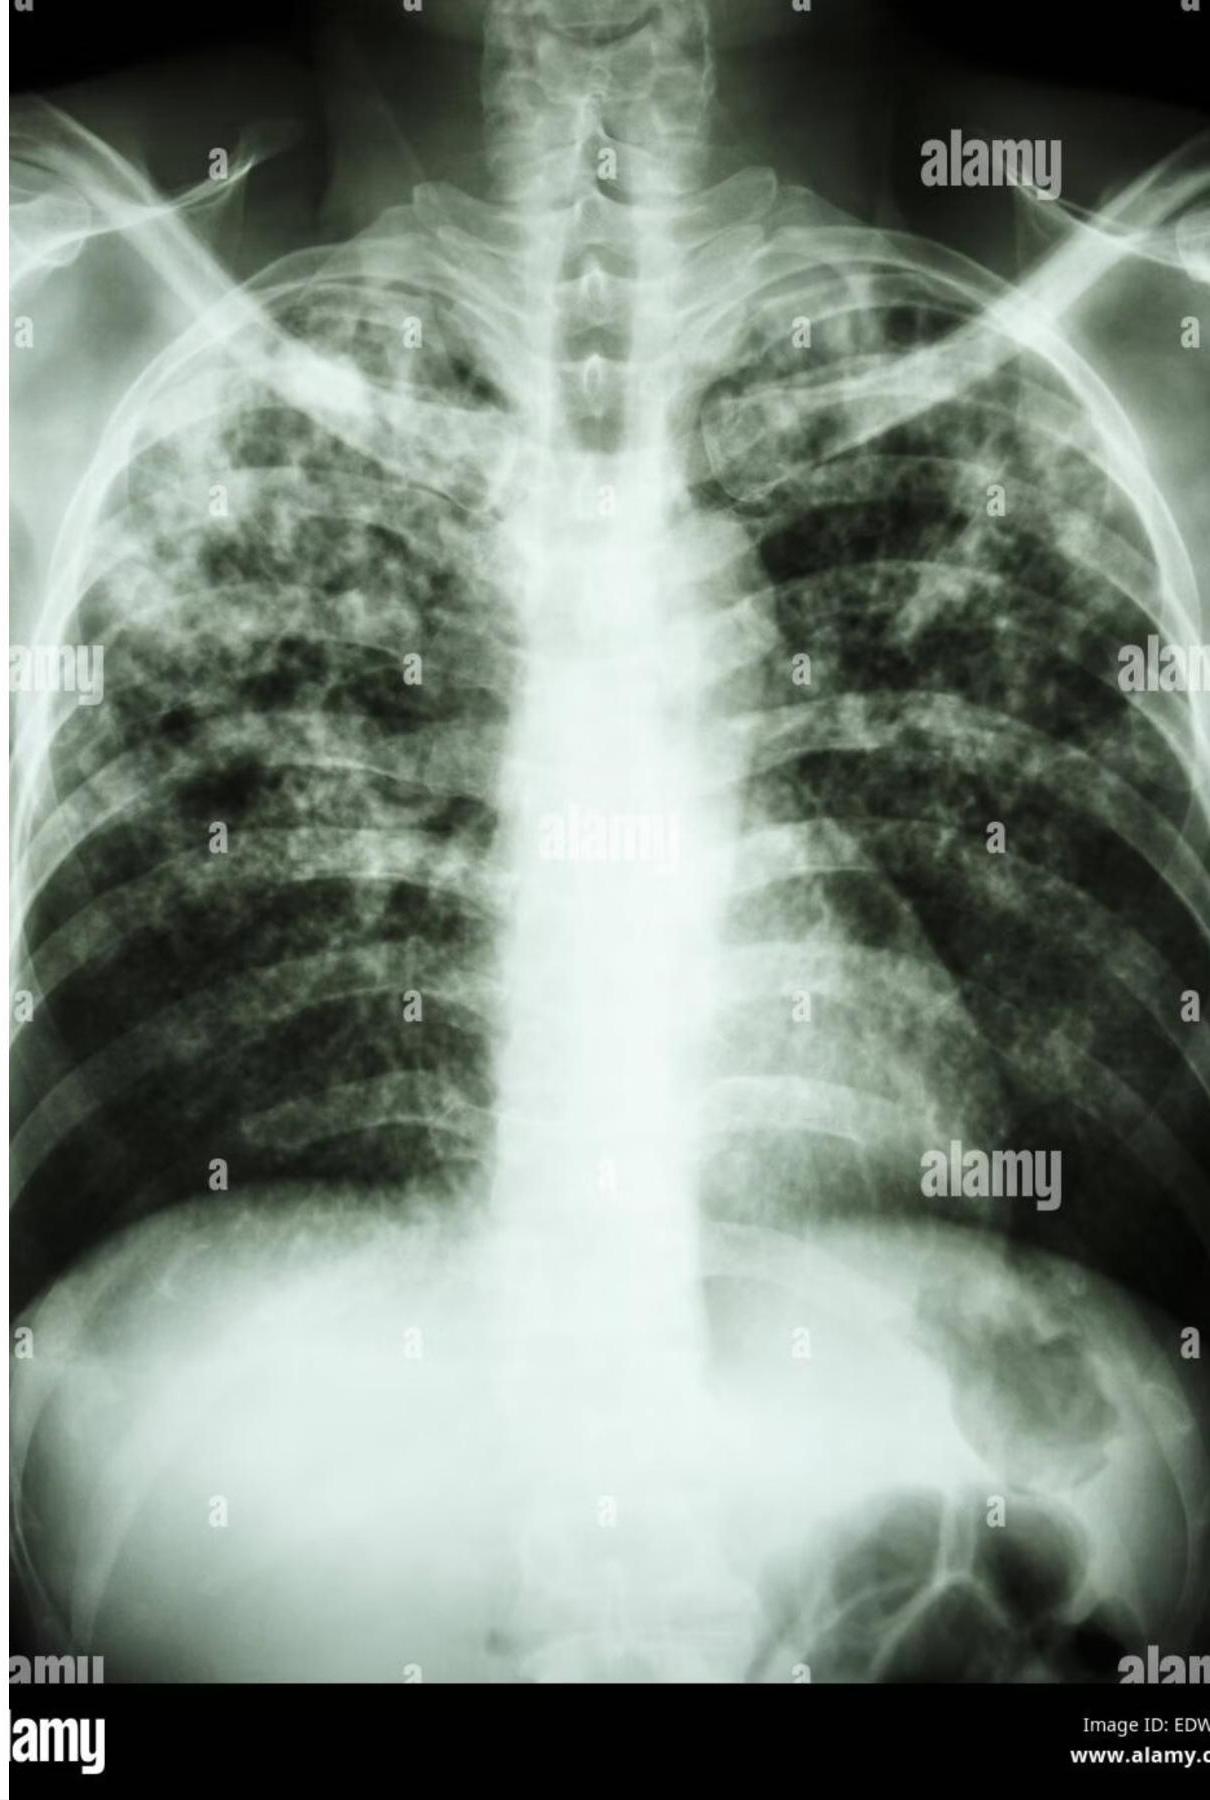

3. Miliary Tuberculosis

- Definition: Widespread hematogenous dissemination to multiple organs; lesions resemble millet seeds.

- Risk: Young/immunocompromised patients.

- Presentation: Fever, general malaise, weight loss, lymphadenopathy, night sweats, hepatosplenomegaly, diffuse bilateral pneumonitis.

- Diagnostics: TST may be nonreactive due to anergy. A live or bone marrow biopsy may be useful for diagnosis when other methods fail.

Chest x-ray showing diffuse bilateral opacities.